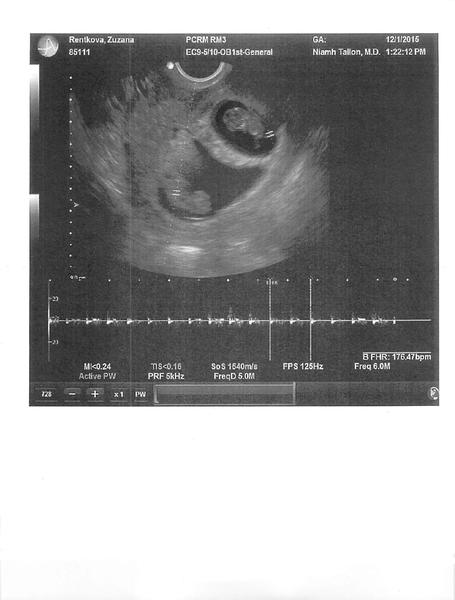

aj ja cakam prve sono 16.12 ...veeelmi pomaly idu tie dni...a to uz od 25.11...cakam...

@chevalbleu ... cakas dvojicky, ci jedno babatko ? 🙂

@hennka2 Dve, to dolu trosku rozmazane 🙂